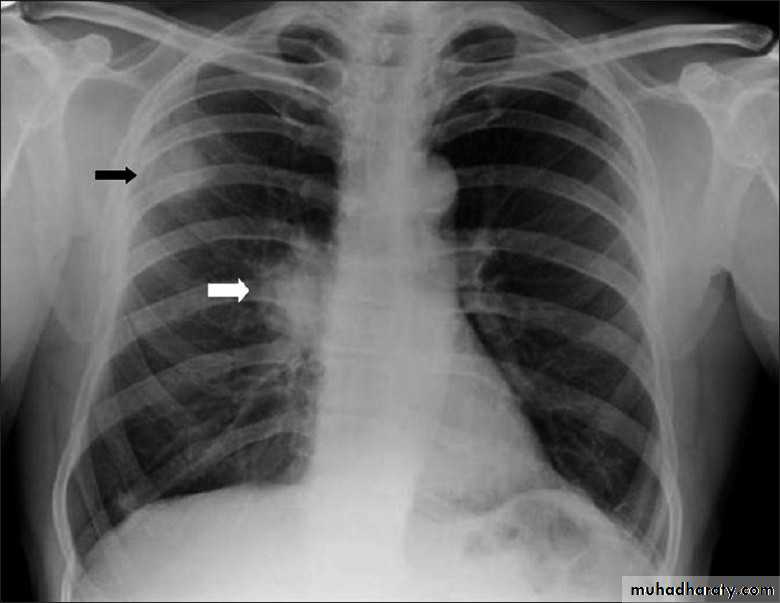

Pleural effusion

50.pleural effusion

51.pleural effusion .